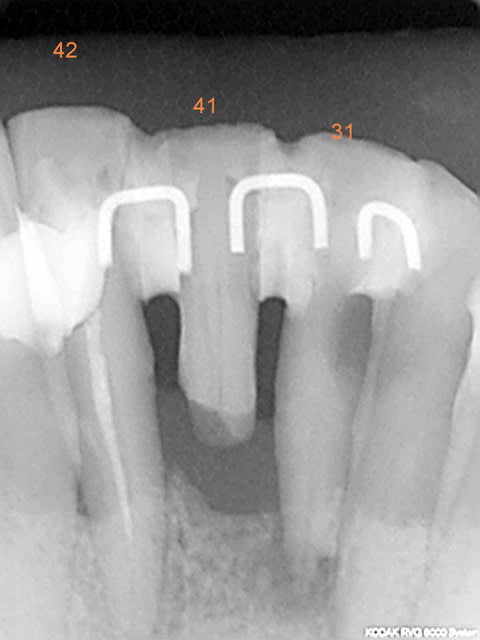

Les attelles d'Abjean j'en pose chaque semaine (ou presque), l'avantage ENOOOOORME par rapport à un "jonc noyé" c'est la rétention 3D que tu n'as pas avec le jonc!

et le délabrement est bcp moindre, en plus quand une attelle lache tu la changes, et pas tout le bastringue!

les miennes tiennent plus de 10 ans...

J'aime beaucoup mon "bridge provisoire" suite à la luxation de la 31 avec fracture de l'apex...^^ elle a tenu 8 ans.

En attendant, ce type de contention transitoire pendant une phase de guérison parodontale après TT ortho (suite aux migrations dentaires) est idéale à mon avis.

3) tu fais une gorge horizontale reliant les 2 points de contact jusqu'à la dentine (prof 1 mm) fraise HL 008

4) un léger avant trou à la fraise boule 008 aux extrémités de la gorge (komet H 009)

5) forage basse vitesse prof 1 à 2 mm les puits doivent être le plus parallèle possible (dans le tiers proximal de la dent à distance raisonnable de la pulpe ;-)

6) confection de l'attelle grâce à une pince à bec plat fine modifiée qui te permet de faire toutes les tailles d'entre-axe

7) essayage et puis souvent réessayage et scellement ou collage si tu en as.

C'est comme cela que Le Pr José Abjean nous l'a appris...à la fac.

C'est joli, mais je trouve que sur les radio, les trous sont plus prodonds que la contention et je trouve cela invasif vs fil ou contention classique. Pour quelques cas bien précis, ok, mais pas trop fréquente l'indication non ?